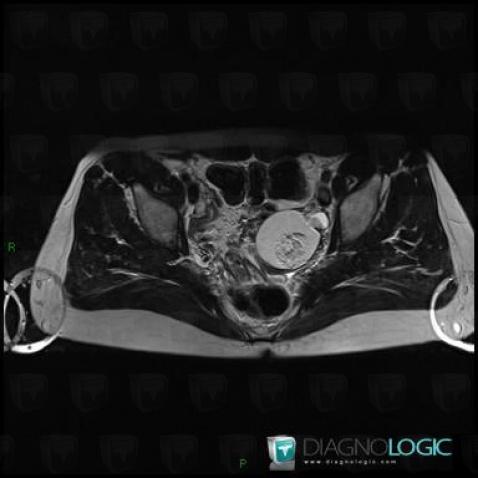

Teratoma, Adnexa / Ovary fallopian tube, MRI

Here is the specific information in the key image above:

- Diagnosis Teratoma (link to Dermoid cyst), Location(s) Adnexa / Ovary fallopian tube, with gamuts Complex adnexal mass, T1 WI hyperintense adnexal mass